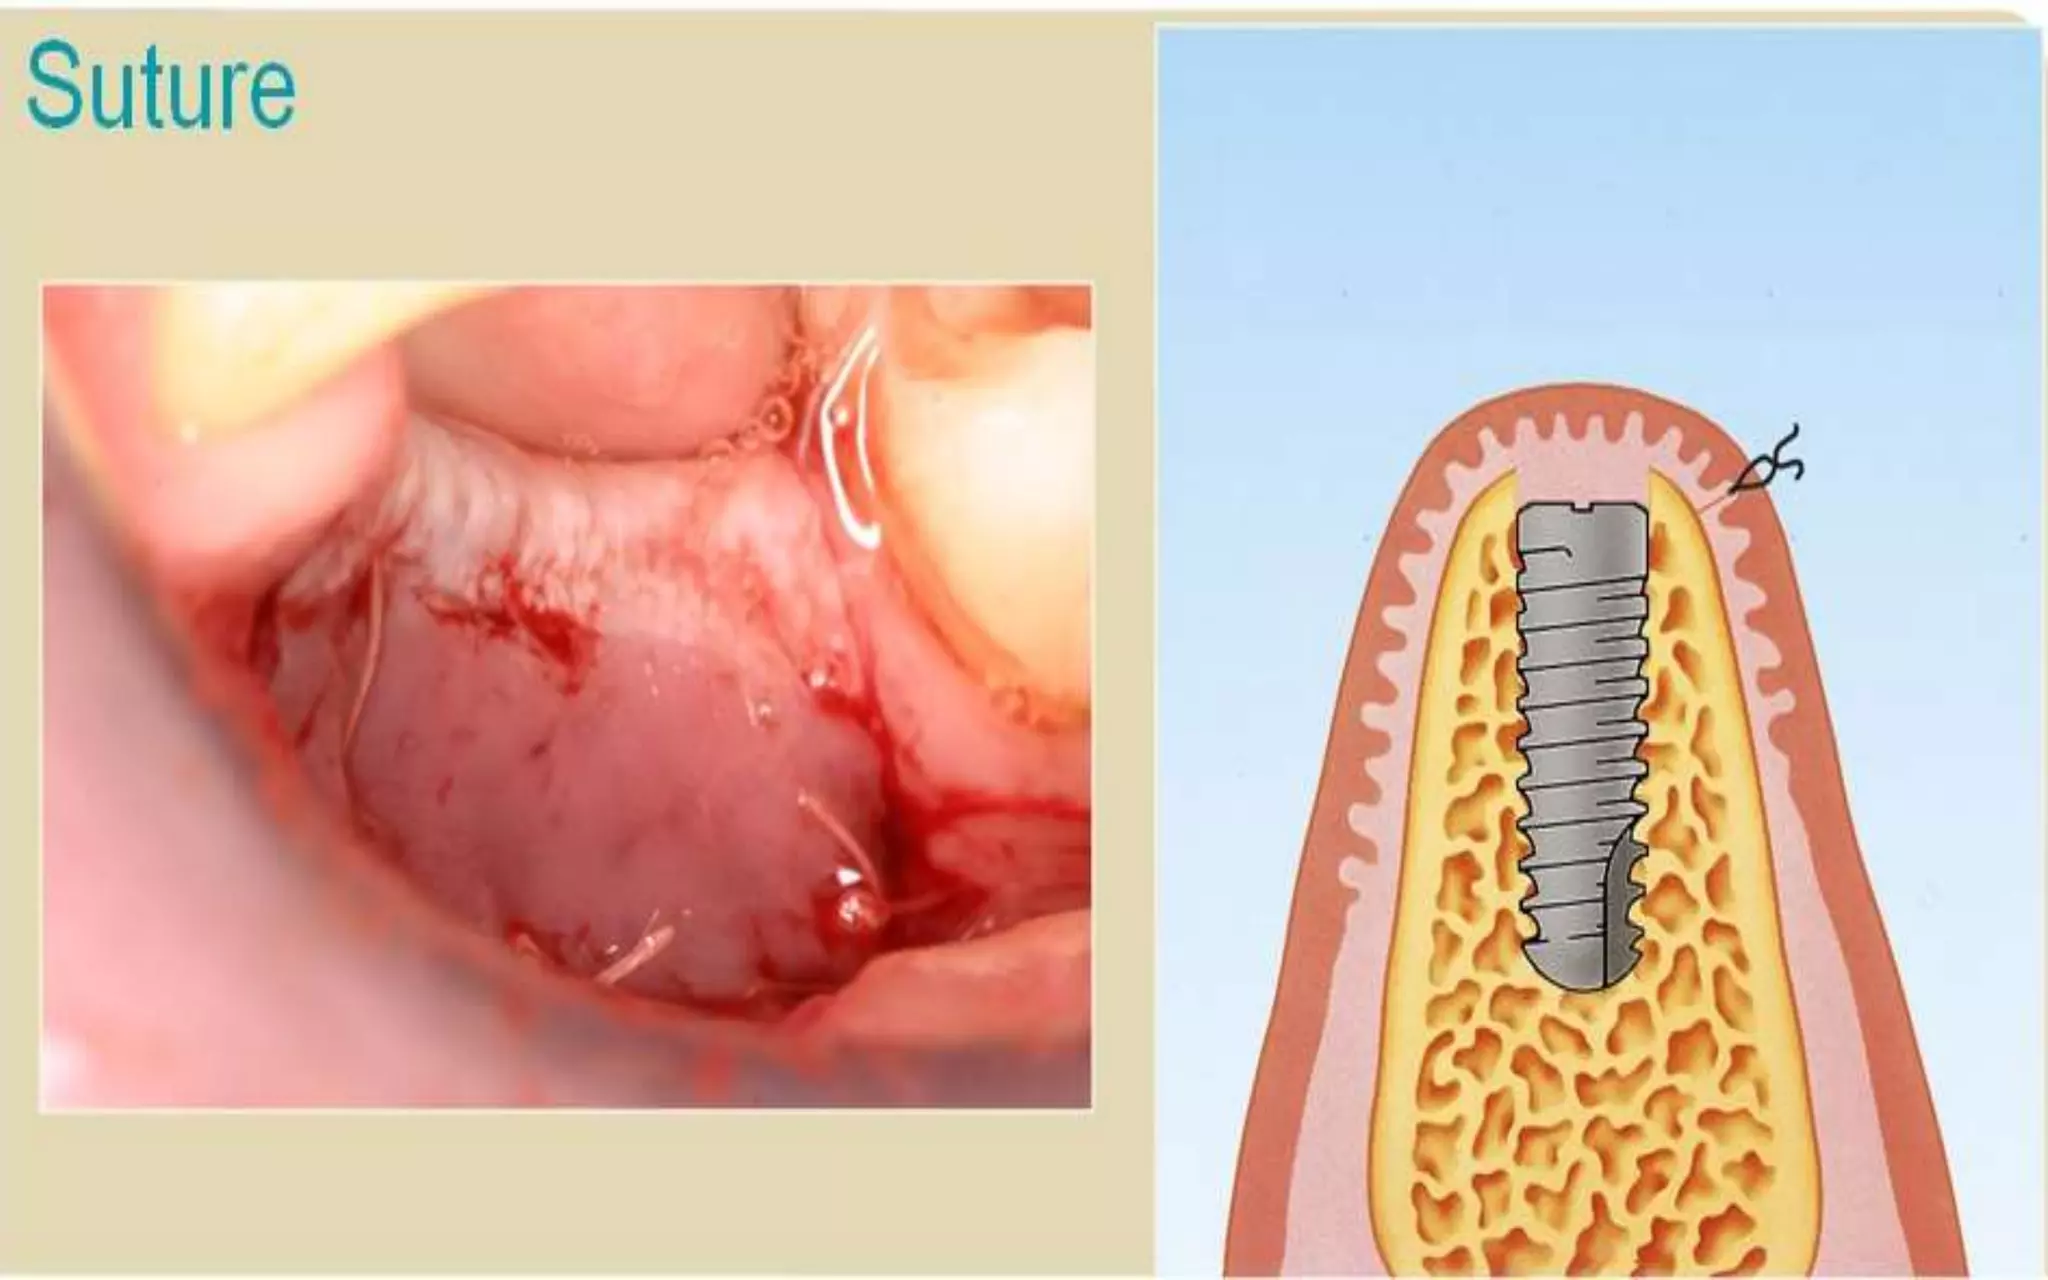

Crestal incision with releasing incisions